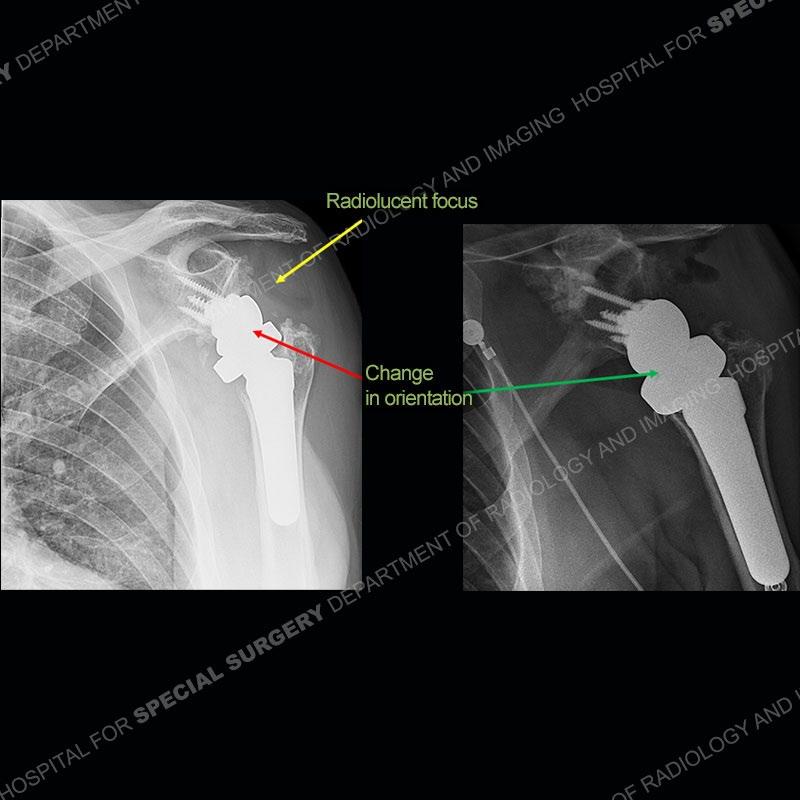

When comparing the radiographs, there is a slight change in the alignment in the components of the prosthesis. On the current radiographs, a radiolucent, crescentic focus is present at the level of the glenoid. When comparing the CT exams, there is a change at the alignment of the glenosphere and the humeral component and now a direct apposition of the components. On the current CT, the radiolucent, crescentic focus is again identified.

If comparison radiographs are present, subtle changes can be made more apparent. Instead of a space between the glenosphere and the humeral tray, there is a direct contact, and there may be an overall change in the alignment at the articulation. The displaced, radiolucent polyethylene liner depending on location can be seen on the radiographs, as in this case. At times, the liner may overlie other structures making identification very difficult on radiographs, but it should almost always be able to be identified on CT (as shown in this example as well). This patient is scheduled for revision procedure.